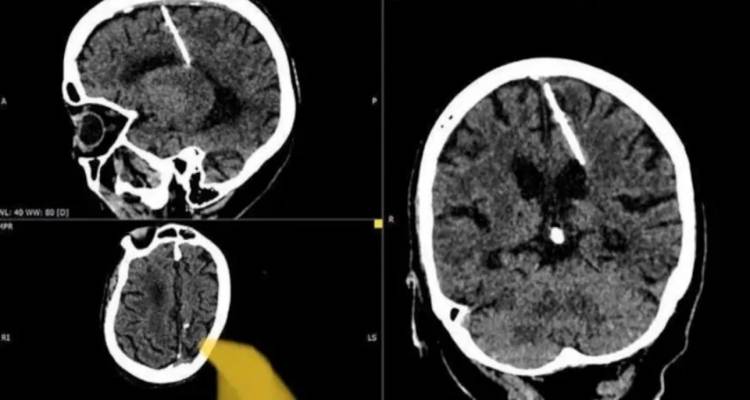

Όπως ανέφερε σε ανάρτησή του στο Telegram το υπουργείο Υγείας της Περιφέρειας της Σαχαλίνης, που βρίσκεται απέναντι από την ανατολική ακτή της Ρωσίας και βόρεια της Ιαπωνίας, ακτινολόγοι ανακάλυψαν τη βελόνα σε ακτινογραφία του εγκεφάλου της γυναίκας εντός του έτους.

Η βελόνα βρέθηκε στον αριστερό βρεγματικό λοβό της γυναίκας που δεν κατονομάζεται, σύμφωνα με το υπουργείο.

Οι αξιωματούχοι είπαν ότι η βελόνα βρισκόταν στον εγκέφαλό της από τη στιγμή της γέννησής της και οι γιατροί πιστεύουν ότι οι γονείς της προσπάθησαν να τη σκοτώσουν όταν ήταν βρέφος.